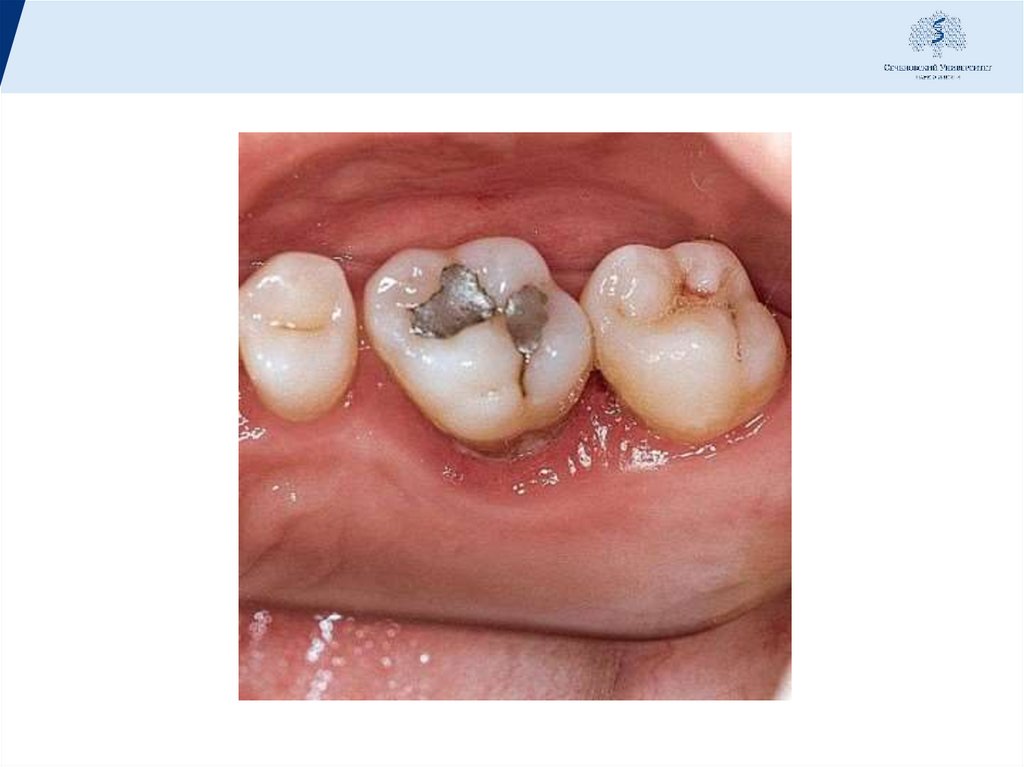

8. Клиника

• Острый очаговый пародонтит по клинической картине

весьма схож с периодонтитом и начинается с

самопроизвольных нерезких болей, кровоточивости десны,

боли при жевании, подвижности зуба. Как правило, в

анамнезе заболеванию предшествовало врачебное

вмешательство - пломбирование зубов, фиксация протезов,

ортодонтическое лечение. Осмотр подтверждает наличие

воспаления десны, кровоточивость, выделение гноя или

серозной жидкости из десневых карманов, которые

образуются в основном вследствие отека тканей. На

рентгенограмме - незначительное расширение

периодонтальной щели, вокруг корня - диффузный очаг

затемнения без нарушения контуров и структуры

компактного и губчатого вещества, за исключением

исчезновения замыкательной пластинки - твердой оболочки

на некоторых участках или по всему периметру.